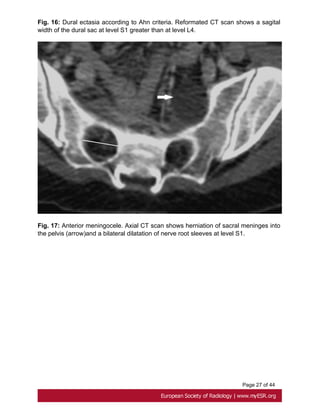

- width of the dural sac at a level below S1 greater than that above L4. Fig. 16 on page

25

- Presence of an anterior sacral meningocele. It is present when there is a herniation of

the dural sac through a defect in the anterior surface of the sacrum or when the sacral

meninges are herniating anteriorly into the pelvis through a widened foramen[26]. Fig.

17 on page 27

Fig. 16: Dural ectasia according to Ahn criteria. Reformated CT scan shows a sagital

width of the dural sac at level S1 greater than at level L4.

Fig. 17: Anterior meningocele. Axial CT scan shows herniation of sacral meninges into

the pelvis (arrow)and a bilateral dilatation of nerve root sleeves at level S1.

Page 10 of44 A less common cardiovascular manifestation of Marfan syndrome is dilatation of the main pulmonary artery. The upper values have been established at 24 mm at the pulmonary artery bifurcation and 34mm at the pulmonary artery root[23]. Fig. 15 on page 24 2- Dural ectasia Dural ectasia (DE) is one of the major criteria of Marfan syndrome in the Ghent nosology. It has a prevalence in Marfan syndrome of about 60% and its severity increases with aging[24]. It is a widening of the dural sac or spinal nerve root sleeves, usually associated with bony erosions of the posterior vertebral body, increased thinning of the cortex of the pedicles and laminae, widening of the neural foramina, or presence of a meningocele[25]. Ahn Criteria Ahn et al. described that dural ectasia is present if one major or two minor criteria are present. Major criteria: - width of the dural sac at a level below S1 greater than that above L4. Fig. 16 on page 25 - Presence of an anterior sacral meningocele. It is present when there is a herniation of the dural sac through a defect in the anterior surface of the sacrum or when the sacral meninges are herniating anteriorly into the pelvis through a widened foramen[26]. Fig. 17 on page 27 Minor criteria: -scalloping greater than 3.5 mm at the level of S1. Fig. 18 on page 27 - nerve root sleeve diameter greater than 6.5 mm at the level of L5[27]. Oosterhof criteria According to Oosterhof et al, dural sac ratio from levels L1 through S1 in adult patients have to be greater than respectively 0.64, 0.55, 0.47, 0.48, 0.48, and 0,57 in dural ectasia. A dural sac ratio is calculated for each level by dividing the sagittal dural sac diameter by the midsagittal vertebral body diameter [28]. Fig. 19 on page 29, Fig. 20 on page 31

Page 27 of44 Fig. 16: Dural ectasia according to Ahn criteria. Reformated CT scan shows a sagital width of the dural sac at level S1 greater than at level L4. Fig. 17: Anterior meningocele. Axial CT scan shows herniation of sacral meninges into the pelvis (arrow)and a bilateral dilatation of nerve root sleeves at level S1.